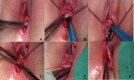

Herlyn-Werner-Wunderlich syndrome (HWWS) is a rare congenital mullerian anomaly consisting of uterus didelphys, hemivaginal septum, and unilateral renal agenesis [1,2]. Most authors reported cases of Herlyn-Werner-Wunderlich syndrome with prepuberal or postpuberal onset with cyclical abdominal pain and a vaginal mass (3-8). Only six cases are reported in Literature with early onset of this syndrome under 5 years (9-14). Our case is about 3 years old girl, with all the features of this syndrome who came to our attention for lower abdominal mass. The aim of this article is to share our experience and focus the attention on the importance of high level of suspicion of HWWS in neonatal period to early diagnosis and treatment. The possible early presentation of this syndrome should be suspected in all neonates (females) with renal agenesia confirmed postnatally or with prenatal diagnosis. It is common, in fact, an error of evaluation with planning of removal of mass, that can damage patients in term of chance for a successful reproductive outcome. For all these reasons, our team consider HWWS as differential diagnosis in newborn with prenatal ultrasonography of a cystic mass behind the urinary bladder in the absence of a kidney and plan a pelvic ultrasound (with aim to identify an uterus, normal or dydhelfus, and presence or absence of pelvic mass), an examination under anesthesia and cystoscopy and vaginoscopy, if it is necessary. A high level of suspicion, indeed, is the key to early diagnosis.